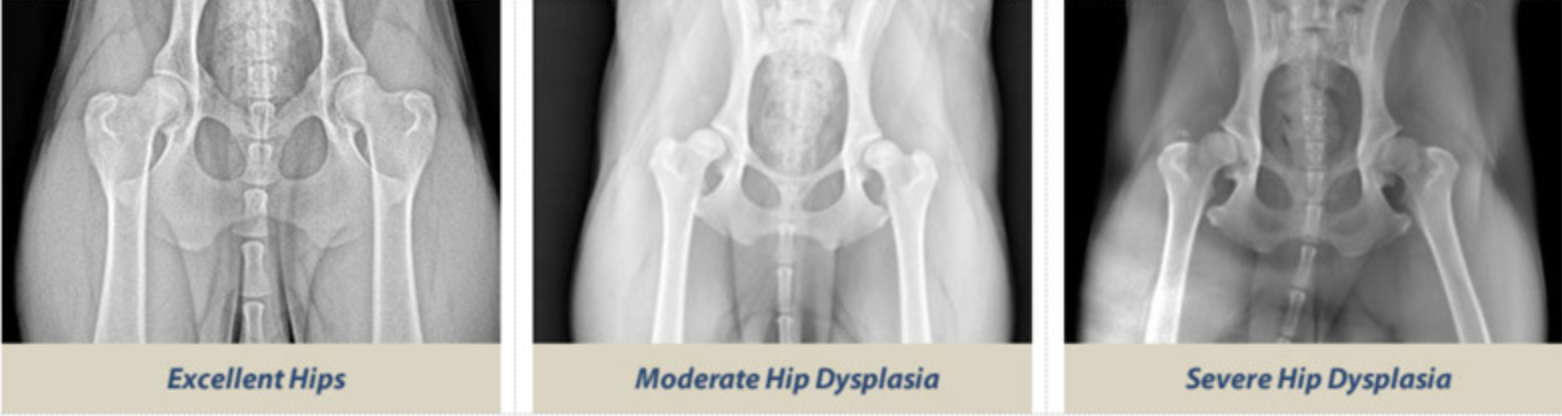

La radiographie : examen de référence

La radiographie est la méthode de référence validée scientifiquement. Elle est réalisée sous sédation ou anesthésie légère. Le relâchement musculaire est recherché. Ainsi, la position articulaire réelle est évaluée.

Plusieurs méthodes internationales sont utilisées chez le chien.

La classification FCI est majoritairement utilisée en Europe.

Les hanches sont classées de A à E :

-

A et B : hanches normales ou quasi normales,

C : dysplasie légère,

D : dysplasie moyenne,

E : dysplasie sévère.

La méthode OFA, surtout nord-américaine, classe également les hanches selon leur aspect radiographique global.

La méthode PennHIP mesure la laxité articulaire réelle.

Elle évalue la capacité de la tête fémorale à se déplacer hors de l’acétabulum.

Cette technique permet une détection très précoce du risque dysplasique.

Ce que le vétérinaire analyse à l’imagerie

Sur les clichés radiographiques, plusieurs critères précis sont évalués :

profondeur de l’acétabulum,

recouvrement de la tête fémorale,

sphéricité fémorale,

symétrie des deux hanches,

signes d’arthrose débutante.

Ces éléments objectivent la sévérité.

Ils orientent aussi la stratégie de prévention dysplasie chien.